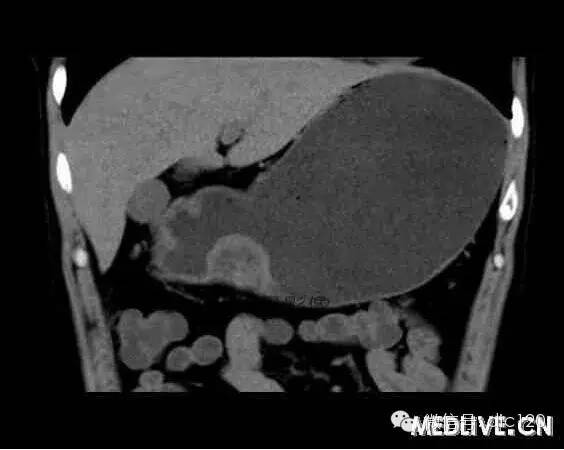

【病例】 胃異位胰腺

男,36歲,間斷性返酸噯氣3年,3個月前出現上腹疼痛,饑餓時加重。圖1-3為CT平掃,圖4-6分別為CT增強掃描的動脈期、門脈期和延遲期。影像表現 CT檢查可見胃幽門前區胃小彎側胃壁局限性增厚、隆起或伴凸向胃腔內的小結節灶,寬基地,境界光整,注射對比劑,增強掃描后,CT值可達50HU以上,與正常胰腺強化相仿?!?確診依據 手術:異位于胃的胰腺 鑒別診斷 1、